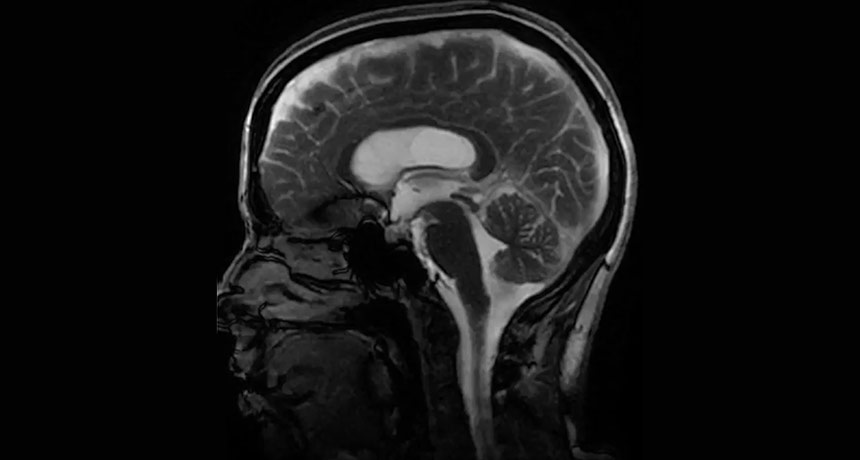

BRAIN IN MOTION By amplifying tiny movements, a new technique reveals how the brain wiggles as fluid moves in and out.

Stanford University and University of Auckland